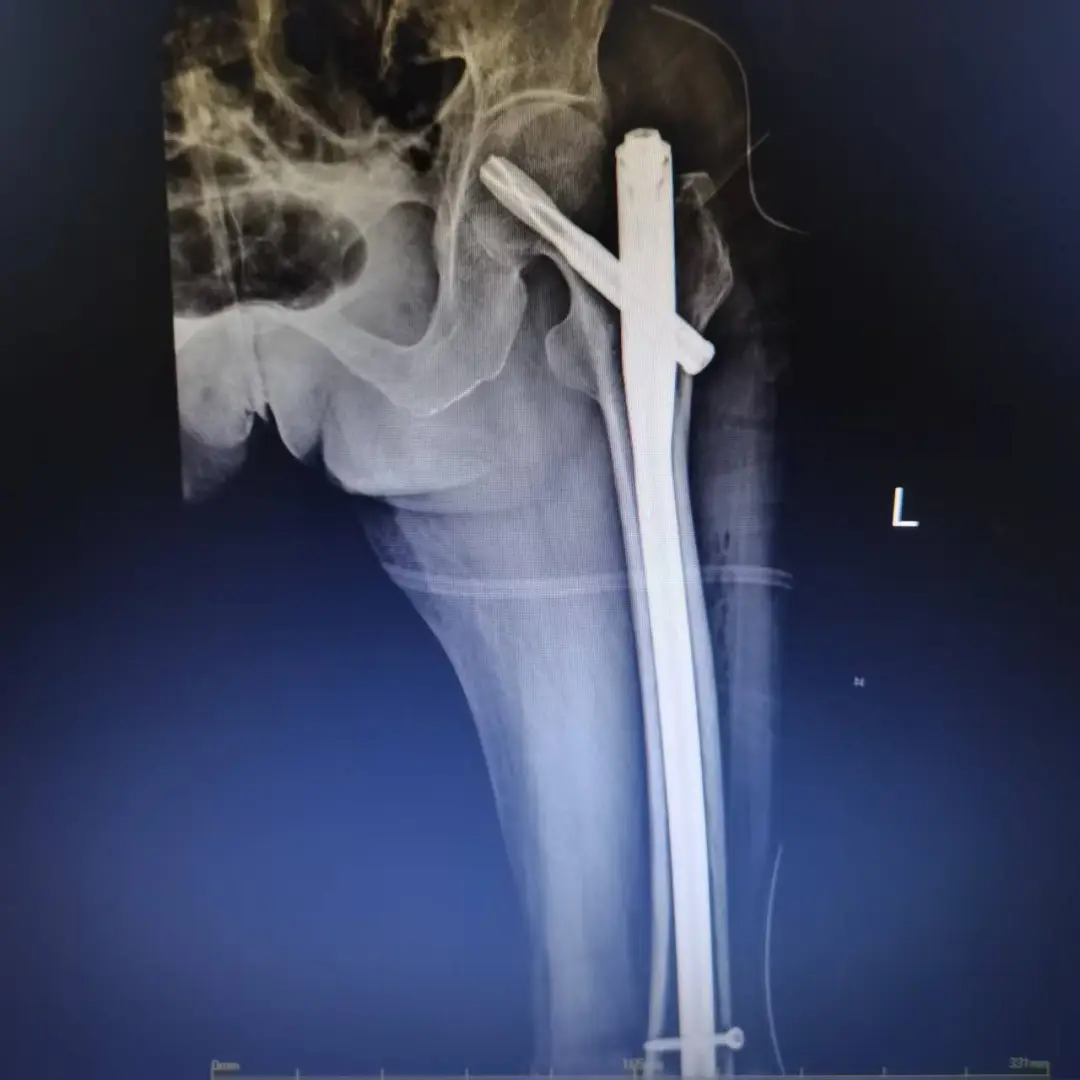

經(jīng)過系統(tǒng)術(shù)前調(diào)理,患者電解質(zhì)紊亂得到糾正,心功能趨于穩(wěn)定。在多學(xué)科團(tuán)隊(duì)評估后,最終排除絕對手術(shù)禁忌癥,確定手術(shù)方案為“左側(cè)股骨髓內(nèi)針內(nèi)固定術(shù)”。該術(shù)式創(chuàng)傷小、固定牢,利于患者早期活動,非常適合高齡患者。

手術(shù)當(dāng)日,麻醉醫(yī)師實(shí)施精準(zhǔn)麻醉并全程嚴(yán)密監(jiān)護(hù),骨科主任王曉楓帶領(lǐng)手術(shù)團(tuán)隊(duì)成功實(shí)施髓內(nèi)釘固定。手術(shù)過程順利,出血量少,患者安返病房。